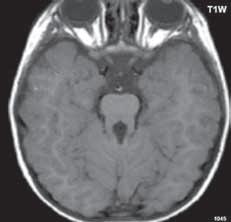

I.1.8 Dandy-Walkerova malformace (D-W variant, D-W komplex, D-W spektrum )

V současné odborné literatuře je nejčastěji užíván termín D-W spektrum, který snad nejlépe vyjadřuje velmi široké možnosti vrozených změn zadní jámy lební. Mezi tuto skupinu cystických malformací zadní jámy lební pak řadíme klasickou malformaci D-W a její varianty, mega cisterna magna, arachnoidální cystu zadní jámy lební a retrocerebelární vak (Blake’s pouch cysta). Zařazení malformace do určité klinické jednotky není někdy jednoznačné, proto je možná výhodnější a přesnější vycházet z přesného popisu zobrazených změn. Příčina D-W malformace není známa, nabízejí se dvě hypotézy: 1. nepropustná spodina IV. komory, eventuálně uzávěr nebo pozdní otevření otvorů, kterými proudí likvor ze IV. komory. 2. primární hypogeneze mozečku. Embryonální vývoj mozečku ze všech hlavních struktur mozku trvá nejdelší dobu, a proto je velmi vulnerabilní k různým patologickým příčinám po dlouhou dobu svého vývoje.

Zobrazení

D-W malformace je charakterizována hypoplazií vermis mozečku, rozšířením IV. mozkové komory, která se často cysticky vyklenuje dorzálně a může imitovat arachnoidální cystu, rozšířením zadní jámy lební a vysokým úponem tentoria s confluens sinum nad lambdovým švem. Okcipitální kost může být vlivem tlakových změn remodelována, existují i případy s porušením její kontinuity a encefalokélou. Hydrocefalus pozorujeme v 80 %, častá je přítomnost dysgeneze corpus callosum, schizencefalie.

Mega cisterna magna je struktura likvorového signálu, lokalizována dorzálně a kaudálně od mozečku, není doprovázena hypoplazií mozečku, rozšířením IV. komory ani hydrocefalem, někdy může být tlakem zeslabená lamina interna lebky v zadní jámě lební. Diferenciální diagnostika mezi mega cisterna magna a arachnoidální cystou je mnohdy obtížná a může nám pomoci CT cisternografie (chybí nebo pozdní pronikání kontrastní látky do arachnoidální cisterny), určité informace může přinést MR vyšetření pulzace likvoru.

Retrocerebelární vak (Blake’s pouch cysta) vzniká embryonálně vyklenutím části stropu IV. komory (velum

mediale superius) do cisterny magna (vak je vyplněn likvorem, chybí foramen Magendii). Je charakterizován rozšířenou a široce otevřenou IV. komorou, která komprimuje bazální cisterny, hypoplazie vermis mozečku naopak není přítomna. Široce komunikující IV. komora (někdy obsahuje choroidální plexus), přičemž komunikace mezi komorovým systémem a subarachnoidálními prostory je pouze přes laterální foramina Luschkae.

Obr. I.1.8h Mega cisterna magna

Obr. I.1.8ch Retrocerebelární vak (Blake’s pouch cyst), široce komunikující IV komora, chybí foramen Magendii